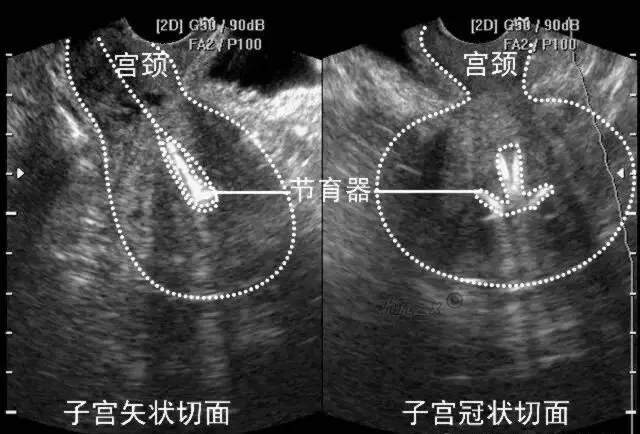

宫内节育器

●声像图表现:宫腔内线性、圆形或三角形强回声。

●宫内节育器位置正常:节育器强回声位于宫腔中心,其周围内膜显示为低回声的晕圈。在子宫纵切面可判断宫内节育器在宫腔内的位置正常位置的宫内节育器应全部位于宫腔内,且节育器最下缘不低于宫颈内口。

宫内节育器位置异常声像图